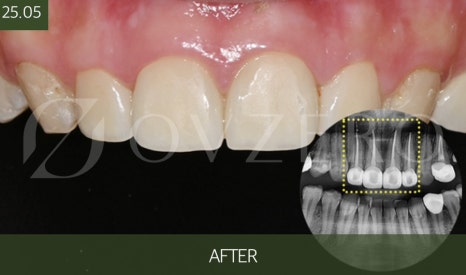

How Is the Treatment Process Carried Out?

Zirconia crown treatment is not as complicated as you might think,

but each step is very important.

First, the tooth condition is examined

and it is determined whether crown treatment is really necessary.

After that, the tooth is prepared

only as much as needed for the crown,

and an accurate impression is taken for fabrication.

While the crown is being made,

a temporary tooth is placed

to help minimize inconvenience in daily life.

Previous image

Once the final crown is completed,

the color, shape, and height are checked,

and after repeatedly checking the bite feel,

it is placed.

This final bite adjustment is

an important step that affects the lifespan of the crown.